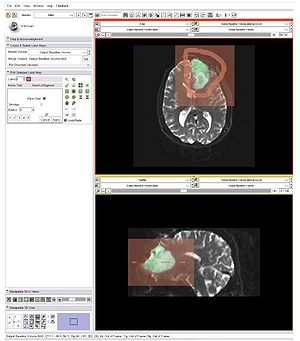

Publication: PLoS One. 2016 Jan 11;11(1):e0145987. PMID: 26751685 | PDF Authors: Zhan Q, Chen X. Institution: School of Mechanical Engineering, Shanghai Jiao Tong University, Shanghai, China. Background/Purpose: This paper proposes an interactive method of model clipping for computer-assisted surgical planning. The model is separated by a data filter that is defined by the implicit function of the clipping path. Being interactive to surgeons, the clipping path that is composed of the plane widgets can be manually repositioned along the desirable presurgical path, which means that surgeons can produce any accurate shape of the clipped model. The implicit function is acquired through a recursive algorithm based on the Boolean combinations (including Boolean union and Boolean intersection) of a series of plane widgets' implicit functions. The algorithm is evaluated as highly efficient because the best time performance of the algorithm is linear, which applies to most of the cases in the computer-assisted surgical planning. Based on the above stated algorithm, a user-friendly module named SmartModelClip is developed on the basis of Slicer platform and VTK. A number of arbitrary clipping paths have been tested. Experimental results of presurgical planning for three types of Le Fort fractures and for tumor removal demonstrate the high reliability and efficiency of our recursive algorithm and robustness of the module. Funding:

A snapshot of the module SmartModelClip in 3D Slicer. On the left is the operator command view that users can create and manipulate clipping path and thickness plane(i.e., they can create, hide and delete plane widgets). Users can also reverse the directions of the axes of the both clipping path and thickness plane widget. On the right is the scene that users can interact with the clipping path. They can specify the fiducial points that position the clipping path and modify the boundary of the clipping path by dragging the handles to obtain the desirable clipping path. |